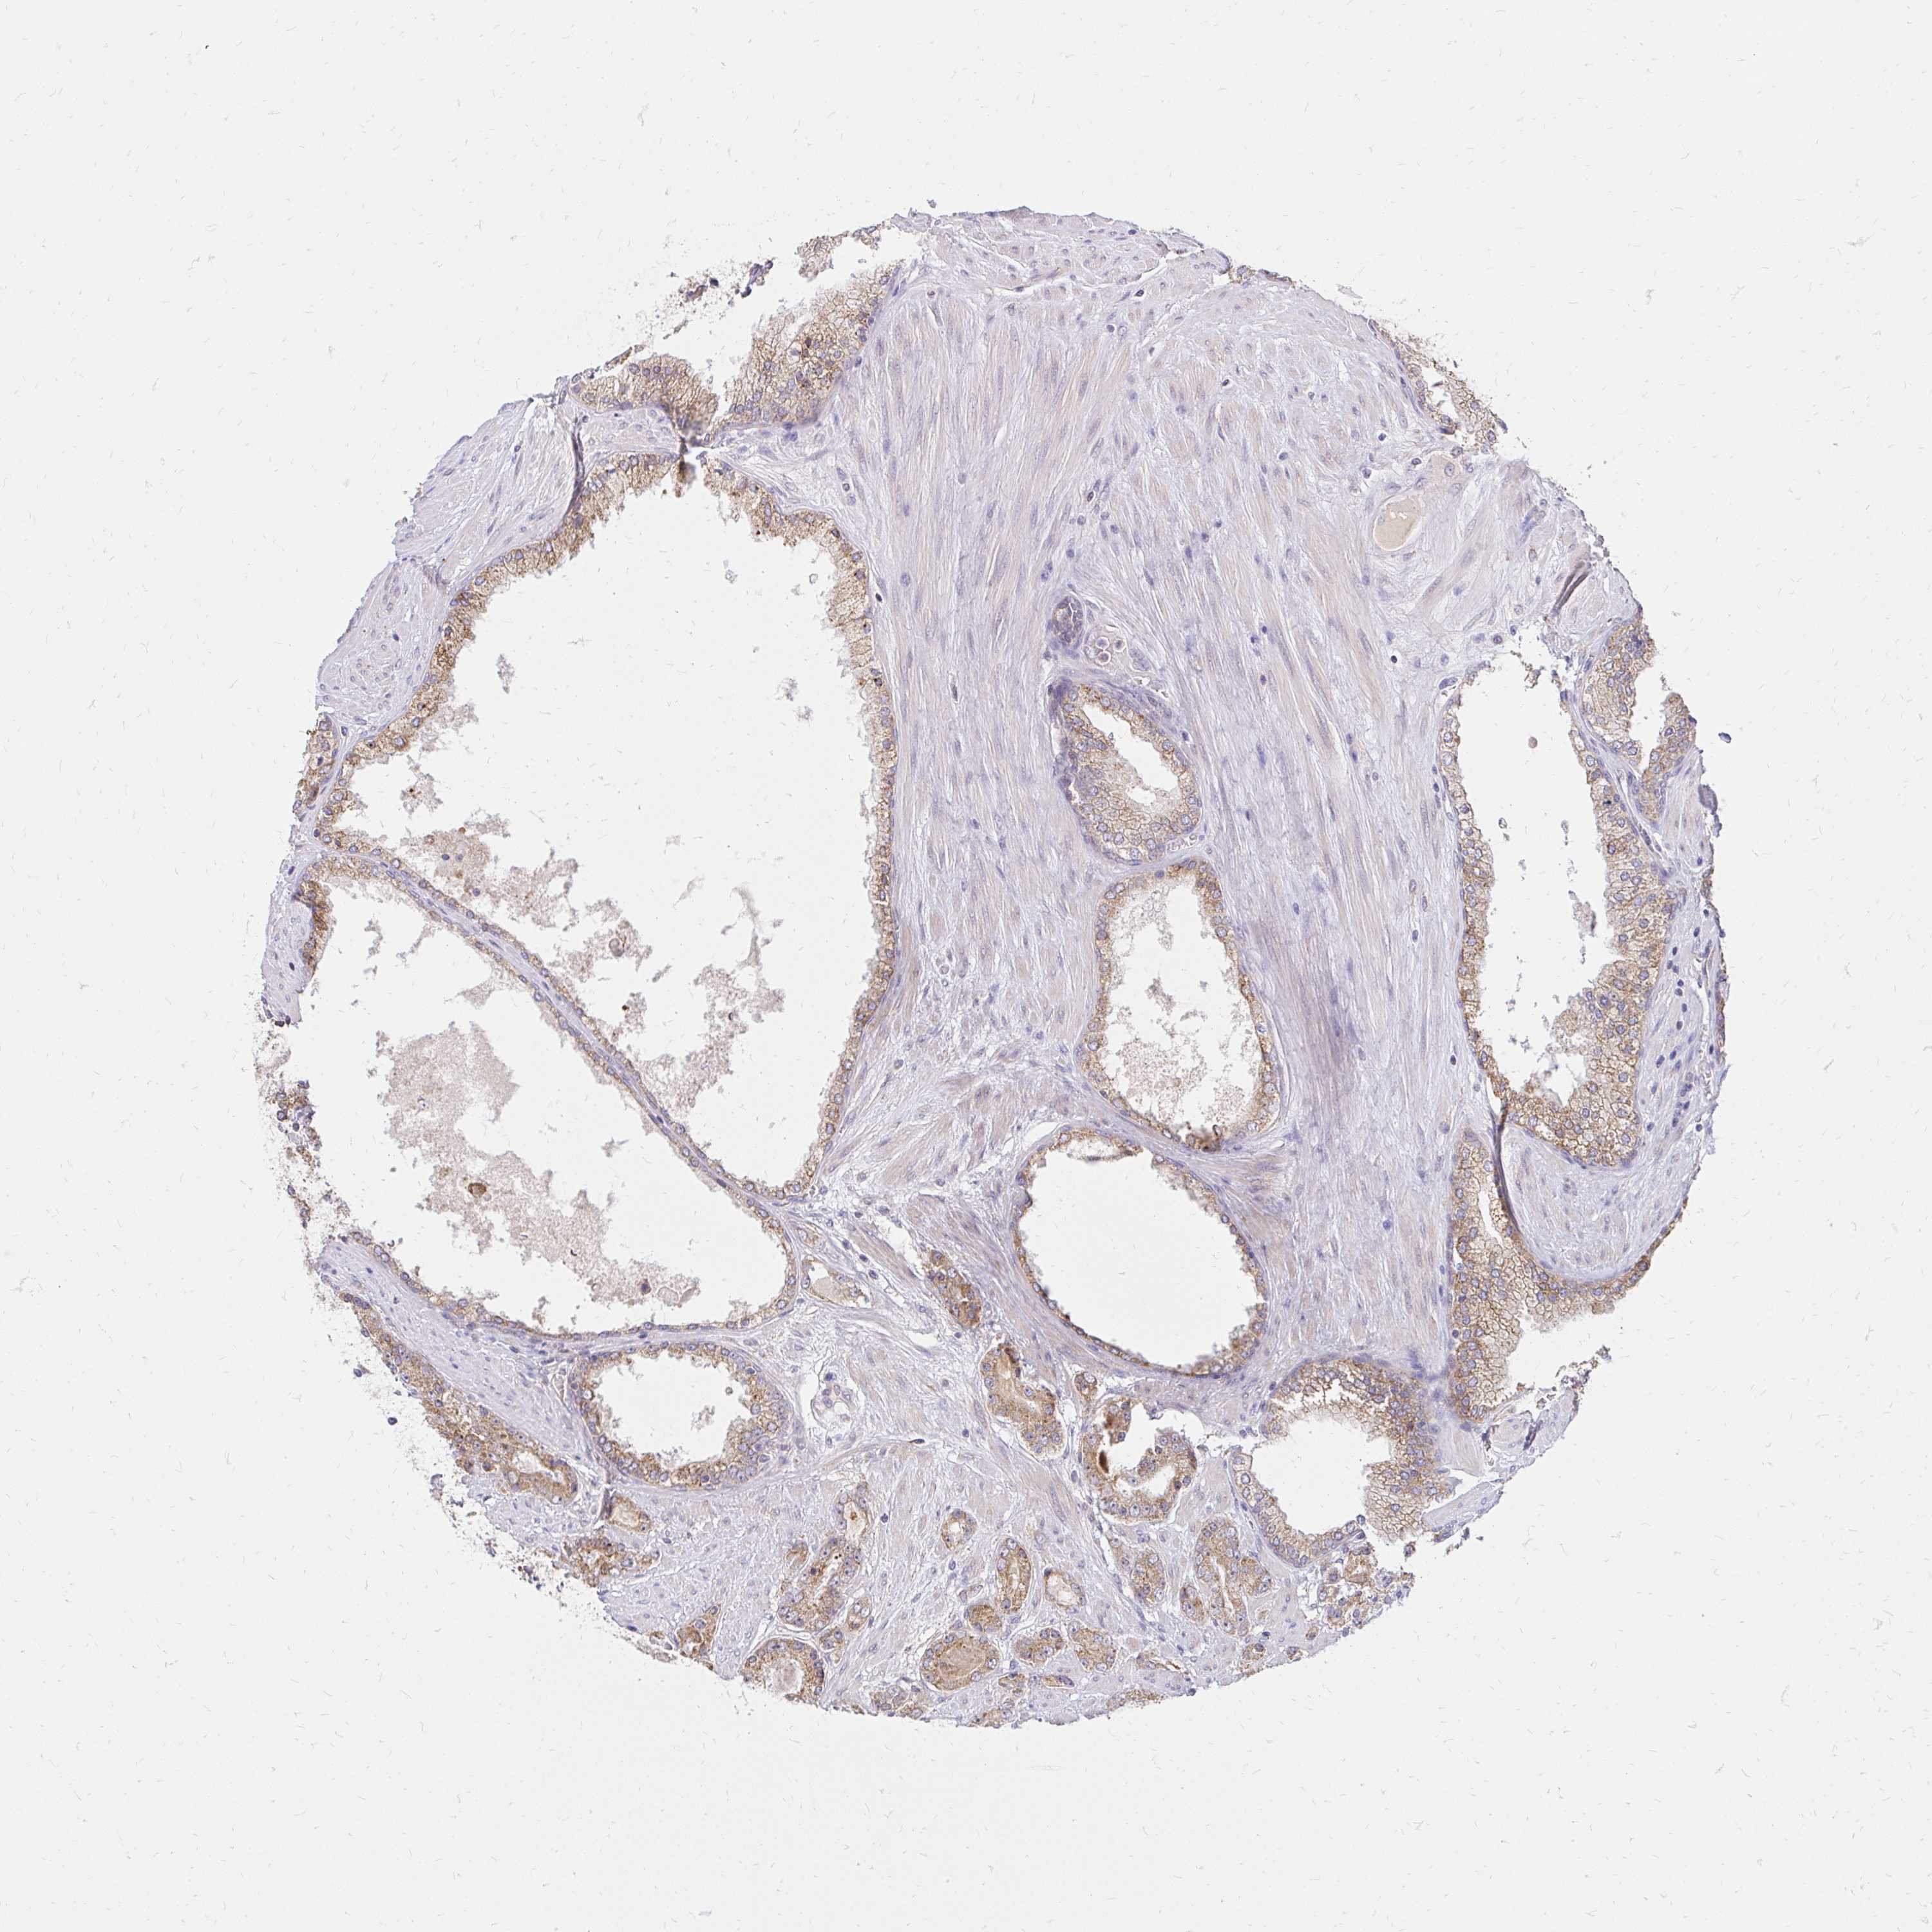

PROSTATE CANCER - Protein expressioni

A mouse-over function shows sample information and annotation data. Click on an image to view it in a full screen mode. Samples can be filtered based on level of antibody staining by selecting one or several of the following categories: high, medium, low and not detected. The assay and annotation is described here.

Antibody stainingi

Antibody staining in the annotated cell types in the current human tissue is reported as not detected, low, medium, or high, based on conventional immunohistochemistry profiling in selected tissues. This score is based on the combination of the staining intensity and fraction of stained cells.

Each image is clickable and will lead to virtual microscopy that enables deeper exploration of all samples and also displays staining intensity scores, fraction scores and subcellular localization as well as patient and tissue information for each sample.

Antibody HPA060820

Adenocarcinoma, High grade

Adenocarcinoma, NOS

Adenocarcinoma, Low grade